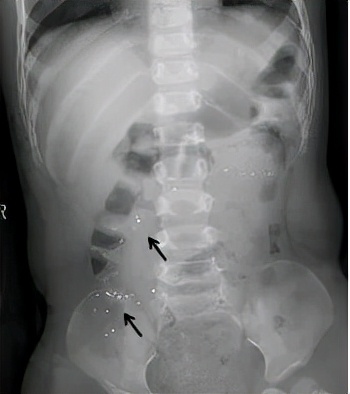

影像科拍片检查,可以清楚看到肚子里的水银颗粒!

6、及时就医,必要时可以拍X线片观察下汞在胃肠道内的部位。